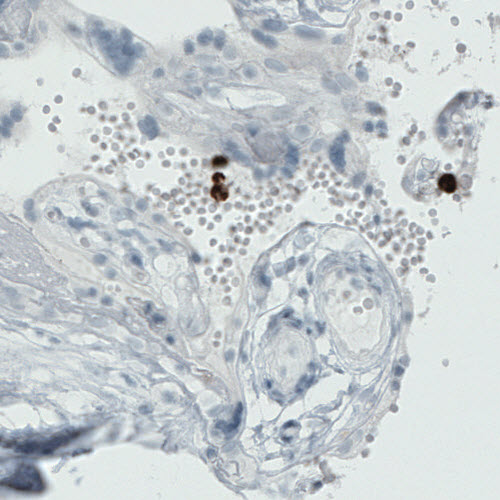

Immunohistochemical staining of human tonsil shows strong immunoreactivity in a subset of lymphoid cells, primarily outside germinal center.